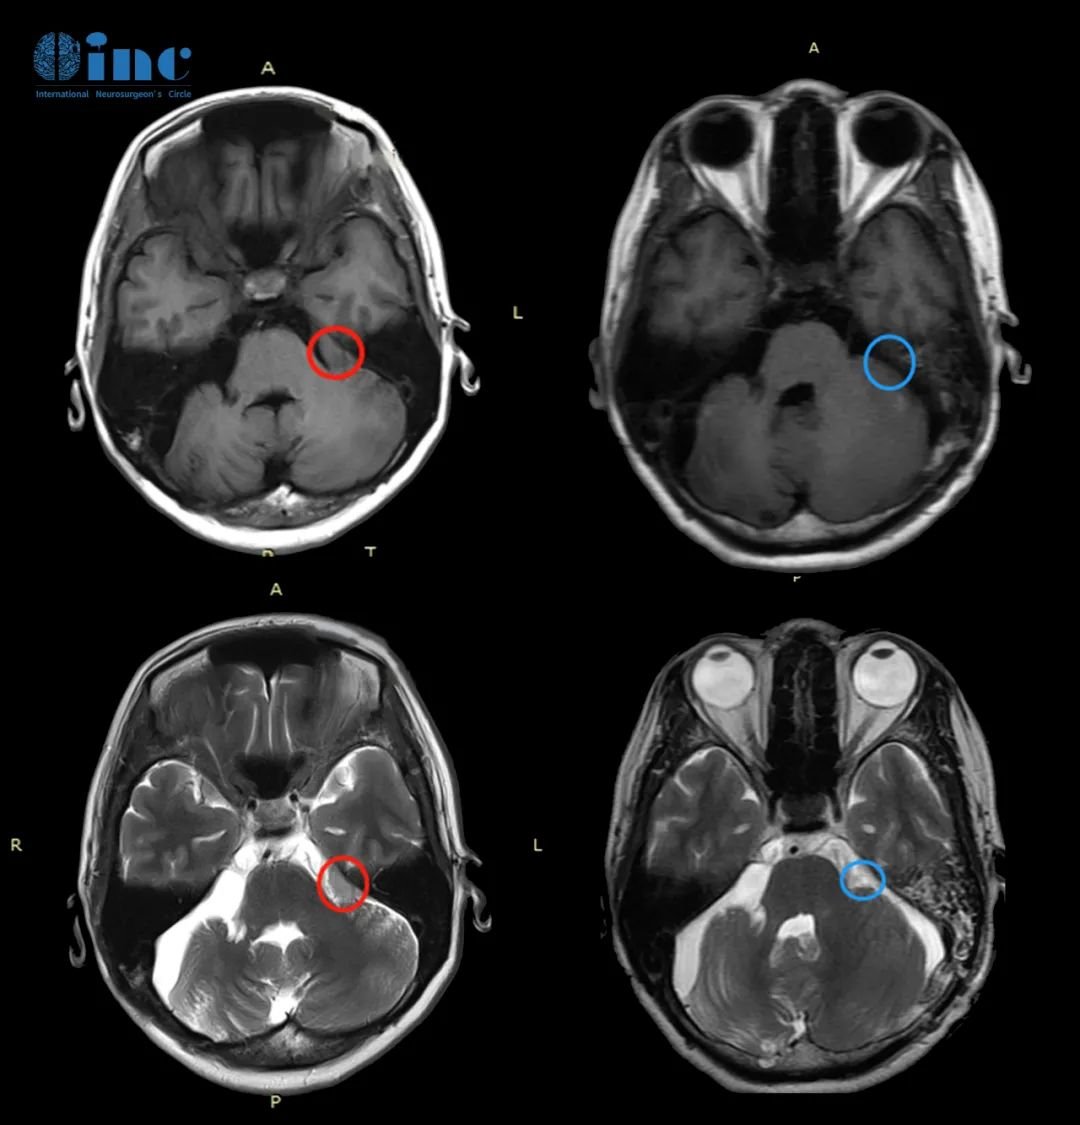

30岁男性-脑干海绵状血管瘤

◉手术时间:2022年11月巴教授疑难示范手术期间

◉患者情况:30岁的脑干海绵状血管瘤患者江先生从2016年1月份开始,头晕、行走不稳,重影复视。2016年至2018年4次出血,18年到23年3次出血。轻微的肢体麻木症状。巴教授了解到江先生病史后评估“的治疗就是手术,自己做过许多类似的病例,96%以上都是恢复的好。对于这类病人,一个好的手术是重要的。”

◉治疗过程:2023年11月5日,巴教授为30岁脑干(桥脑)海绵状血管瘤患者江先生成功手术,术后1天转出ICU,状态良好,无新发功能障碍。

◉术后情况:术后一天查房,转出ICU,转入普通病房,恢复状况良好。巴教授查房时用中文询问道“今天感觉怎么样?”“Very very good!”,巴教授逐一检查了江先生的吞咽、面部活动、肢体活动等功能,“没问题”,巴教授为江先生的状态点赞。“Thank you very much!”,江先生及家人都无比感谢巴教授。